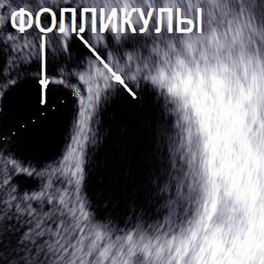

Одним из довольно распространенных методов дородовой диагностики заболеваний у будущего малыша является такая процедура, как кордоцентез плода. Суть манипуляция заключается в заборе крови из пуповины внутриутробного плода с последующим ее исследованием разными методиками. Обычно кровь берется для проведения цитогенетического исследования, но иногда могут быть использованы и другие методы диагностики. Метод может использоваться для выявления определенных генетических нарушений, состояний крови и инфекций. Кордоцентез также может быть использован для доставки крови и лекарств ребенку через пуповину.

Кордоцентез, на каком сроке делают

Если планируется кордоцентез, на каком сроке делают этот анализ, тоже имеет важное значение. Проводить кордоцентез представляется возможным, начиная с 20 недели беременности, но оптимально проводить исследование в сроке 22-25 недель, как и предусмотрено законодательством. Но при наличии показаний его можно провести как раньше, примерно с 18 недель, так и в более поздние сроки, хотя это связано с техническими трудностями.

Кордоцентез, или чрескожный отбор пуповинной крови, является процедурой, которая может использоваться как в диагностических, так и в терапевтических целях. Наиболее распространенными показаниями являются изоиммунизация и неиммунные отеки; менее распространенным является непосредственное введение лекарств плоду. В случаях аутоиммунной тромбоцитопении у новорожденных метод кордоцентеза исторически использовался для диагностики и оценки реакции плода на терапию у матери. Тем не менее, достигнут огромный прогресс в профилактическом лечении этого расстройства у матери с помощью внутривенного введения иммуноглобулина и преднизолона; серийный кордоцентез больше не рекомендуется. Забор крови плода может использоваться для подтверждения того, что количество тромбоцитов плода достаточно высоко для безопасных вагинальных родов у пациенток, желающих избежать кесарева сечения. Кордоцентез и внутриматочная трансфузия до сих пор широко используются в случаях подозрения на анемию плода. Забор крови плода должен быть выполнен для подтверждения диагноза перед внутриутробным переливанием и должен быть сделан в ультразвуковом отделении, или, если плод жизнеспособен, в обстановке, где при необходимости может быть выполнено срочное кесарево сечение.

Марина, здравствуйте. Амниоцентез – это инвазивная диагностика генетической патологии у плода во время беременности, которая проводится в специальном учреждении путем исследования амниотической жидкости. Ее получают путем пункции и получения околоплодных вод с соблюдением всех правил асептики и антисептики под контролем УЗИ. Опасность данного метода врачи объясняют тем, что есть угроза отслойки плаценты, угрозы прерывания беременности, травмы плода, кровотечения, а также инфицирования его. Избежать все это можно только в том случае, если соблюдать сроки выполнения, проводить манипуляцию специалистам высокого уровня квалификации, а также максимально бережно.

Амниоцентез осуществляется только врачами под контролем УЗИ с соблюдением всех правил асептики и антисептики. Исследование лучше всего проводить в месте, где нет плаценты и сосудов, чтобы минимизировать развитие осложнение и снизить их риск. Для безопасности исследования околоплодных вод сегодня помимо специальной иглы существуют и специальные адаптеры, позволяющие строго контролировать глубину, на которую игла проникает в матку. После получения амниотической жидкости в обязательном порядке контролируют состояние плода и плаценты.